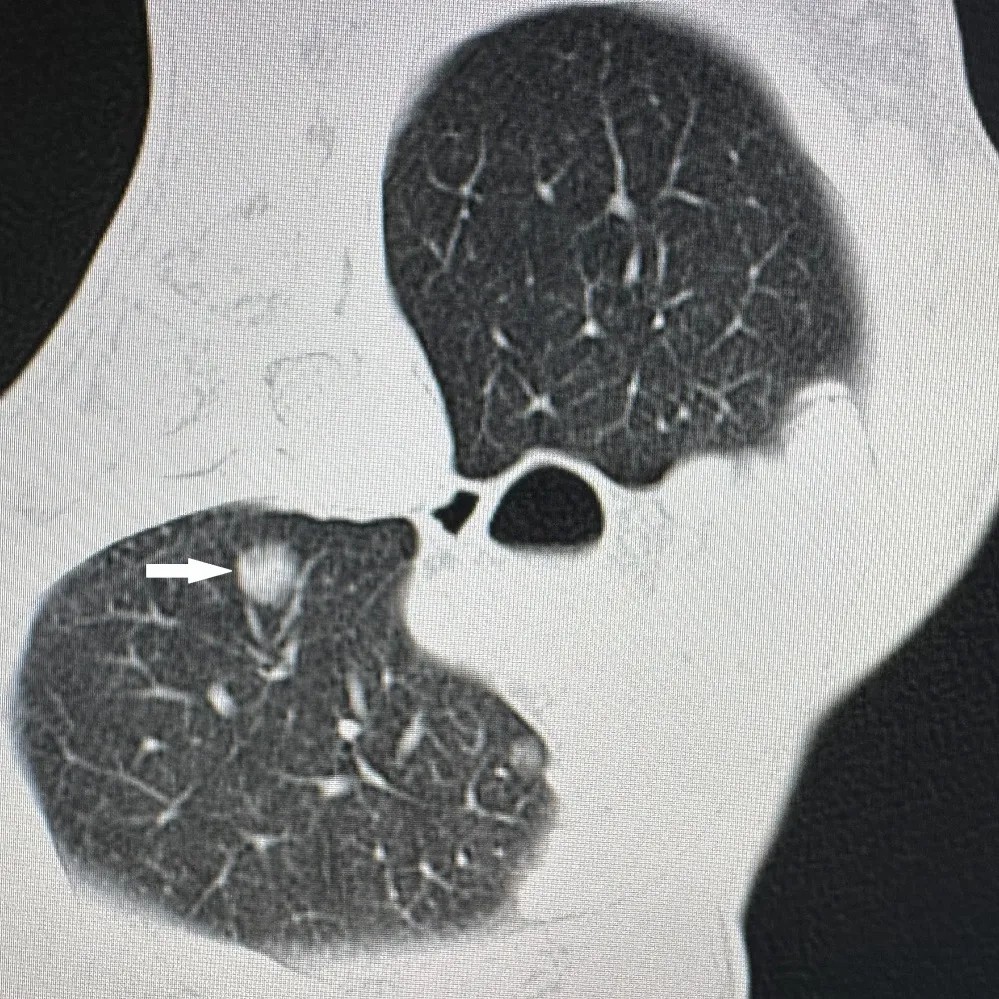

胸部CT显示肺上病灶一个位于肺上叶,因病灶位置较高,肋间隙较窄,比邻肩胛骨,给穿刺造成明显困难;另一个病灶紧邻主肺动脉,穿刺出血风险极高。7月25日,李建军主任经过仔细读片,认真分析,选择了最佳的穿刺路径,通过CT引导,在次旺晋美医师辅助,扎西次仁和德吉卓嘎护士配合下,一次手术对两个病灶进行了精准消融,术后CT扫描显示病灶完全坏死,未出现气胸等并发症,患者安返病房。

肺上叶病灶(白色箭头)